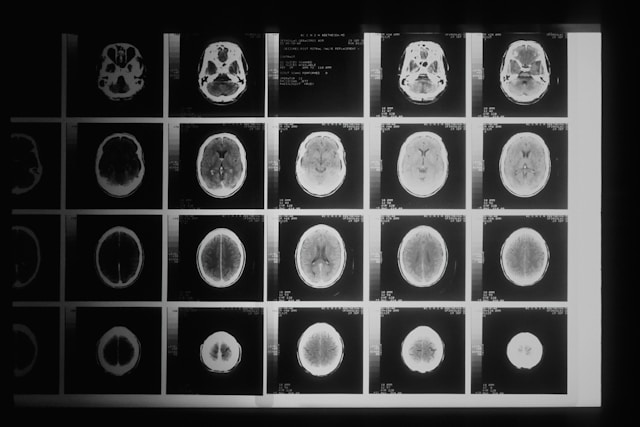

В новых рекомендациях определены точные сроки выполнения рентгенографии или компьютерной томографии (КТ) при ОРВИ, что отсутствовало в старом документе.

При длительности инфекции более 3-5 дней выполняется рентгенография или спиральная КТ при явлениях бронхита или подозрении на бактериальный синусит. Диагностическое исследование также проводят при физикальных признаках поражения легочной ткани.